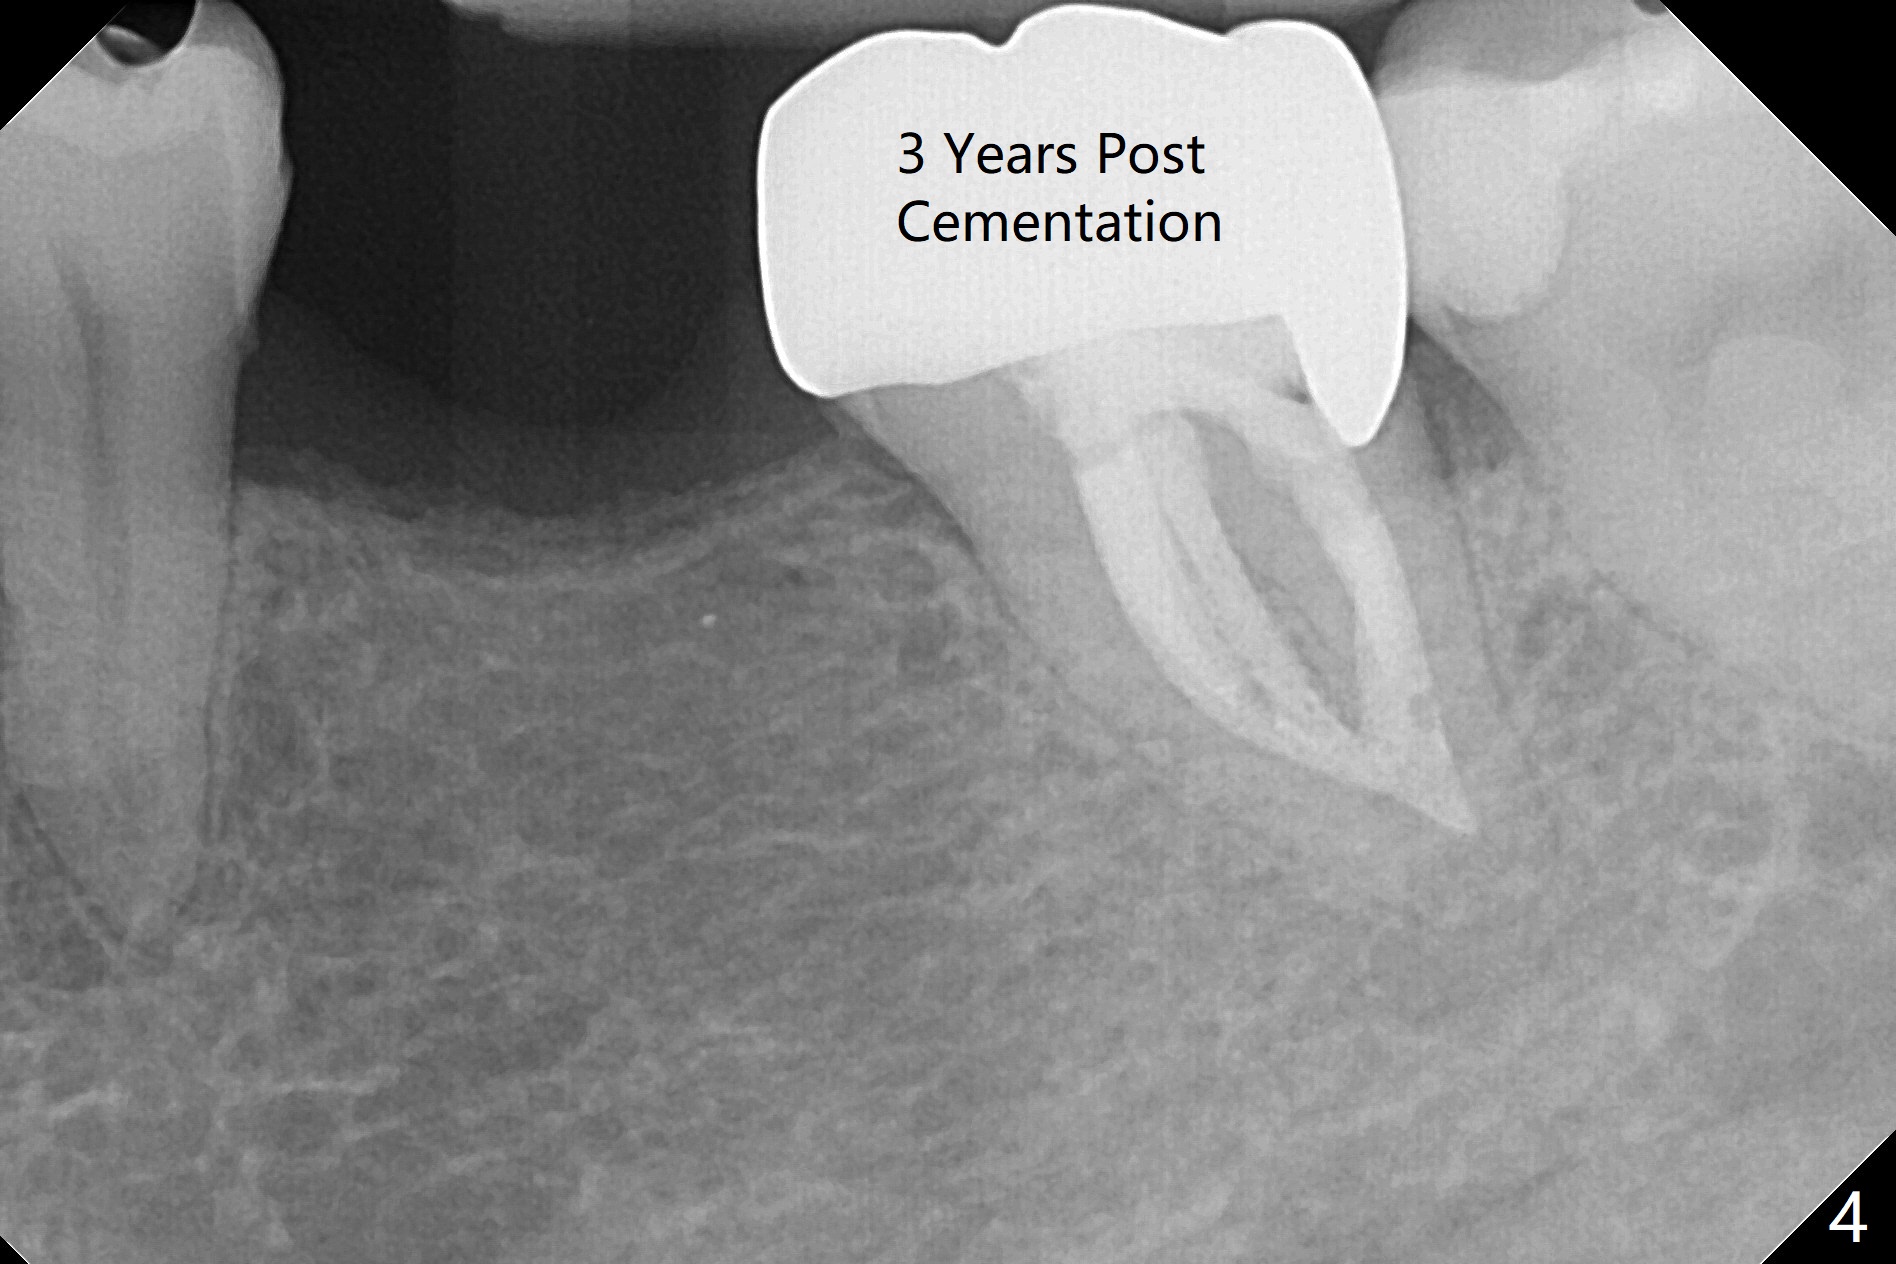

56岁女右上6植牙4年,牙冠松动两次,基台断裂一次,一直不肯做左下6植牙(图一,二,四),对合牙长长(图三:箭头;图五),因为害怕神经(图一:红虚线)损伤,导板已经介绍。IBS No Caries Xin Wei, DDS, PhD, MS 1st edition 11/20/2020, last revision 11/22/2020